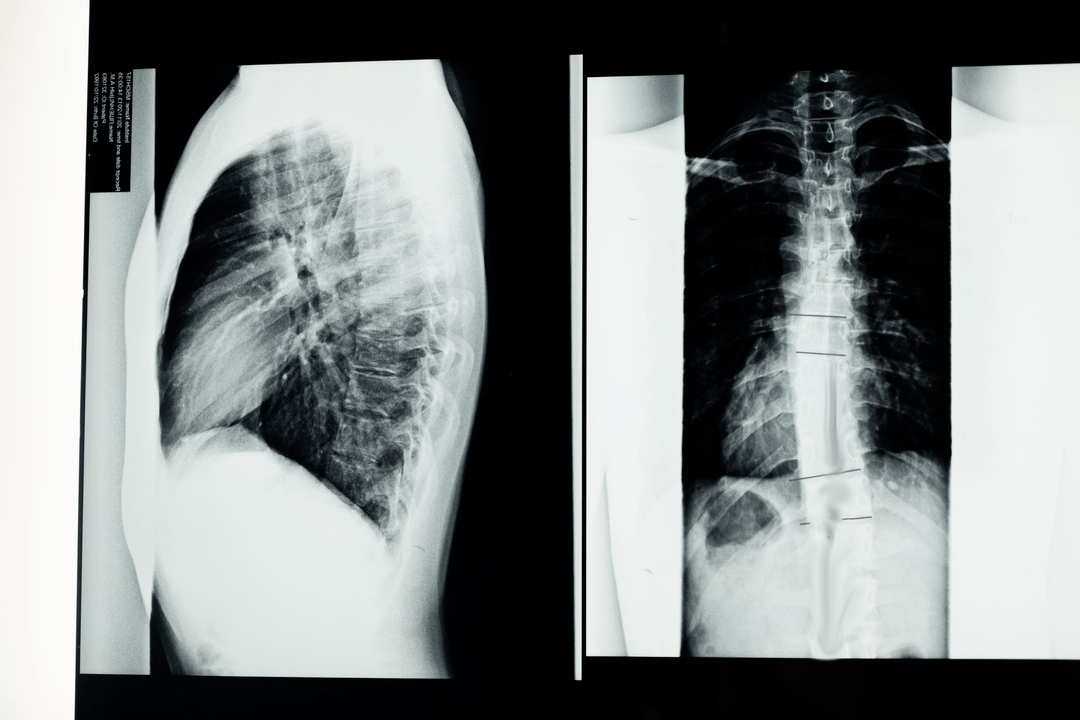

Antes de comenzar los estudios de diagnóstico, el neurólogo recopila el historial médico del paciente y estudia cuidadosamente sus quejas. La osteocondrosis tiene síntomas comunes con algunas otras enfermedades, por lo que es importante poder diferenciar patologías. Los estudios de rayos X ayudarán a confirmar el diagnóstico de osteocondrosis: radiografía, mielografía y tomografía computarizada.

Una radiografía de estudio le permite obtener una imagen de rayos X de la columna o de una sección de ella. De esta forma, el médico puede determinar el lugar afectado por la enfermedad. Para mayor claridad, explicaremos cómo se puede determinar la osteocondrosis mediante rayos X: la imagen mostrará un estrechamiento del disco intervertebral, la presencia de crecimientos óseos (osteofitos) o un cambio en la forma del segmento espinal.